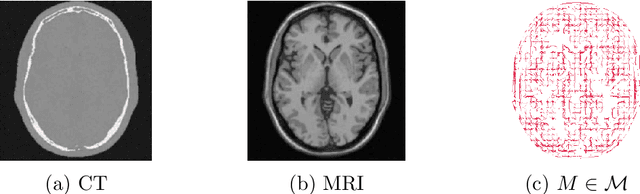

Abstract:In this work we continue studies of the uncertainty quantification problem in emission tomographies such as PET or SPECT. In particular, we consider a scenario when additional multimodal data (e.g., anatomical MRI images) are available. To solve the aforementioned problem we adapt the recently proposed nonparametric posterior learning technique to the context of Poisson-type data in emission tomography. Using this approach we derive sampling algorithms which are trivially parallelizable, scalable and very easy to implement. In addition, we prove conditional consistency and tightness for the distribution of produced samples in the small noise limit (i.e., when the acquisition time tends to infinity) and derive new geometrical and necessary condition on how MRI images must be used. This condition arises naturally in the context of misspecified generalized Poisson models. We also contrast our approach with bayesian MCMC sampling based one one data augmentation scheme which is very popular in the context of EM-type algorithms for PET or SPECT. We show theoretically and also numerically that such data augmentation significantly increases mixing times for the Markov chain. In view of this, our algorithms seem to give a reasonable trade-off between design complexity, scalability, numerical load and asessement for the uncertainty quantification.